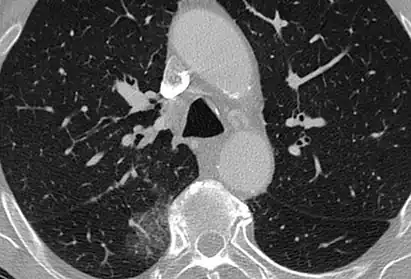

CT image showing diffuse GGOs throughout both lungs. An abscess is also noted in the right lung (screen left). - Adenocarcinoma in situ of the lung